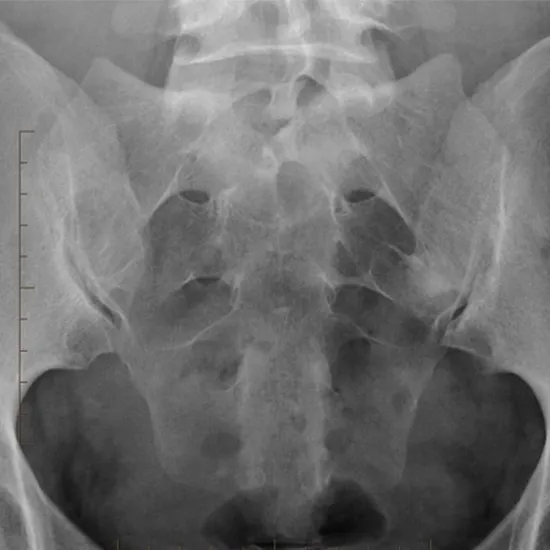

X-RAY SI (sacroiliac) Joint AP View is a radiography procedure that is used to view the area of the back where the spine link with the hip bones. To detect the underlying problems, the doctor recommends this procedure.

Why is X-Ray SI (Sacroiliac) Joint AP View done?

• This non-invasive procedure of X-Ray SI( sacroiliac) Joint is recommended for the patients with lower back pain to detect and diagnose the root cause

• Suspected sacroiliitis

• Suspected ankylosing spondylitis

• For suspected infection, deformities, abnormal growth, or fracture of the bones in the region where the spine and hip connect.